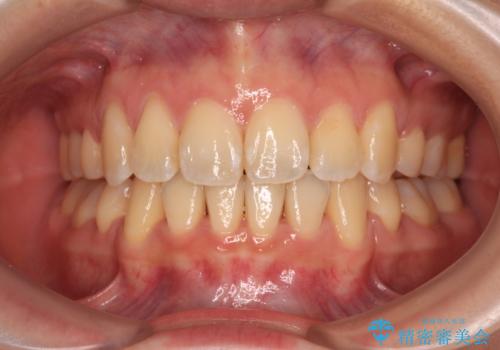

補助装置を併用したおかげでスムーズに奥歯の咬み合わせを改善することができ、我々も予想できないくらい理想的な仕上がりにすることができました。